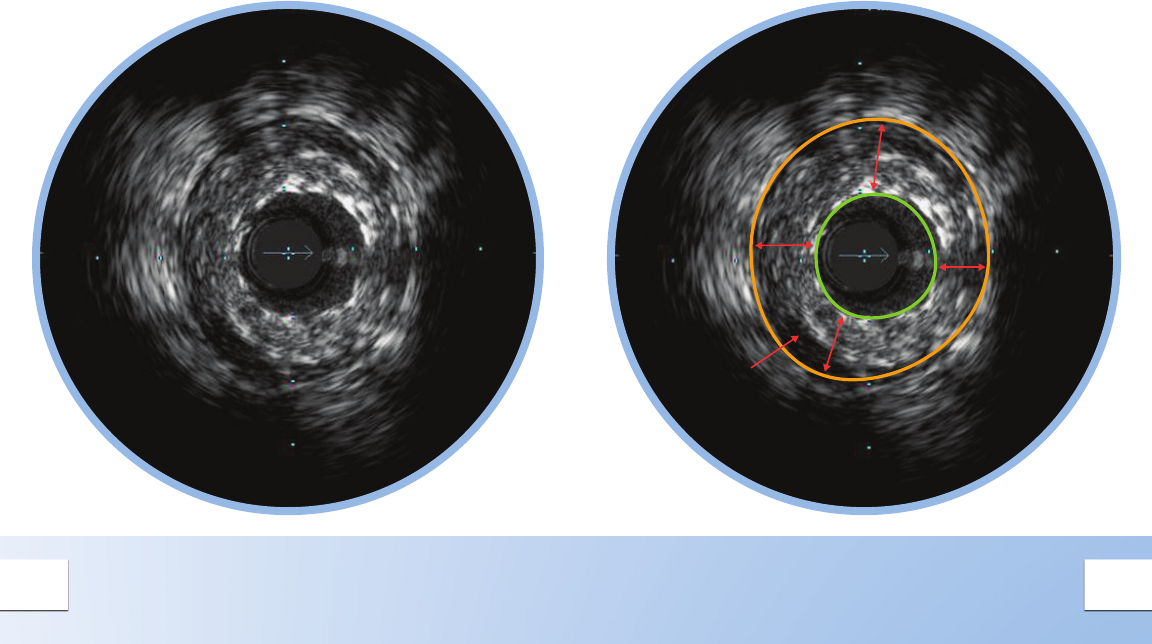

CONCENTRIC MIXED PLAQUE

Concentric plaques are distributed

circumferentially in the vessel.

Concentric plaques tend to occur in areas of

negative remodeling; use of angiography alone

could result in too large a stent diameter.

Mixed plaque is a combination of tissues of varying

echogenecity. The distribution of light and dark

may be distinct, or light and dark variations may be

intermingled as shown here.

Minimum Lumen Area (MLA) can dene a threshold

for a signicant stenosis to determine the need for

catheter-based or surgical intervention.

• MLA < 4 mm2 in LAD, LCX, and RCA vessels > 3

mm in diameter correlates with physiological

signicance1

• MLA < 6 mm2 in left main correlates with FFR <

0.75 indicating physiological signicance1,2,3